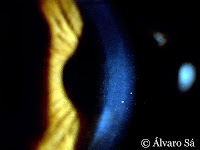

O crescimento de novos vasos (neovascularização) na periferia da córnea (micropannus) é frequente nos portadores de lentes de contacto “diárias” ou “mensais” (hidrófilas).

Este tipo de neovascularização é causado provávelmente pela hipóxia (diminuição acentuada da oxigenação) e pelo traumatismo crónico do limbo (zona periférica da córnea adjacente à esclera responsável pela constante renovação das suas células), que provocam a libertação de mediadores angiogénicos (favorecem o crescimento de neovasos).

Um crescimento destes neovasos inferior a 2mm é aceitável, mas se eles se extenderem mais de 2mm para dentro da córnea, o uso de lentes de contacto deve ser imediatamente descontinuado.

Pormenor dos neovasos que avançam em toda a periferia da córnea num portador de lentes de contacto.